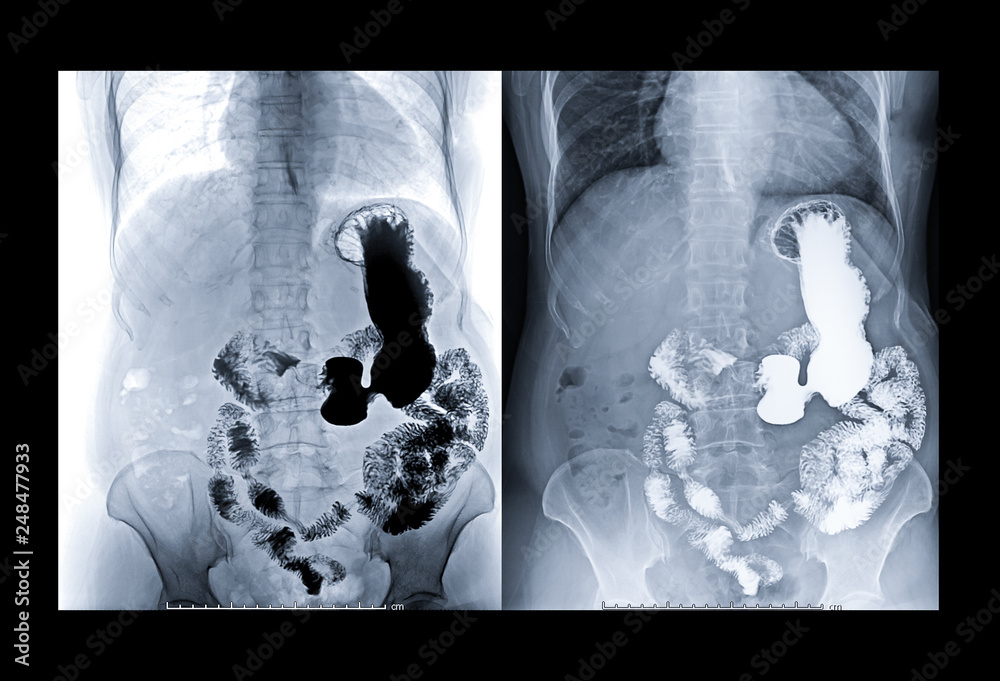

Barium Enema Fluoroscopic Xray of the Lower GI Tract Scientific Fluoroscopy Gastro this scan is used to study the function of your digestive tract, and can show the oesophagus, stomach and small bowel processing a meal. fluoroscopy is an x‐ray procedure that produces live pictures that appear on a screen instead of taking a permanent still. — upper gi studies are a fluoroscopic evaluation of the esophagus, stomach, and. Fluoroscopy Gastro.

Fluoroscopic Examination Lower Gastrointestinal Gi Tract Stock Photo Fluoroscopy Gastro — fluoroscopy is uniquely suited for the evaluation of dynamic oropharyngeal function, esophageal morphology, motility, mucosa,. fluoroscopy is an x‐ray procedure that produces live pictures that appear on a screen instead of taking a permanent still. this scan is used to study the function of your digestive tract, and can show the oesophagus, stomach and small bowel. Fluoroscopy Gastro.